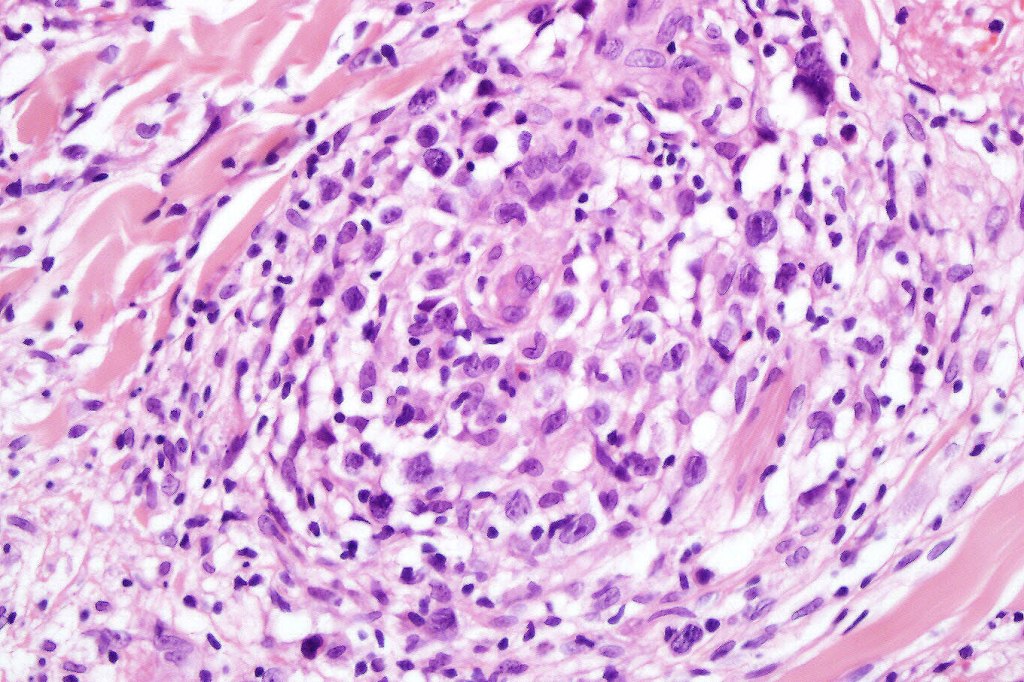

•Type A: 75-80%, wedge shaped infiltrate with base uppermost, large, anaplastic cells with abundant cytoplasm and vesicular nuclei containing prominent nucleoli, can resemble Reed-Sternberg cells, conspicuous mitoses & background infiltrate of lymphocytes, plasma cells, histiocytes, neutrophils & eosinophils

•Type C: 7-10% nodular infiltrate similar to primary cutaneous anaplastic large cell lymphoma